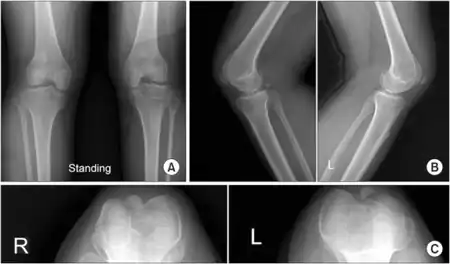

a)Shows small patellae with abnormal morphology b) both knees showing small patellae c) both knees showing small patellae

Ischiopatellar dysplasia is usually identified through radiographic evidence since its characteristic changes are most notable in radiographic tests that indicate delayed bone age or absent ossification.[25] A full skeletal survey should be performed on any patient that has an absent or hypoplastic patellae since they could potentially have ischiopatellar dysplasia. Magnetic resonance imaging (MRI) is especially helpful in the diagnosis of ischiopatellar syndrome and is recommended when an individual affected by ischiopatellar dysplasia has a traumatic injury to the knee.[26]